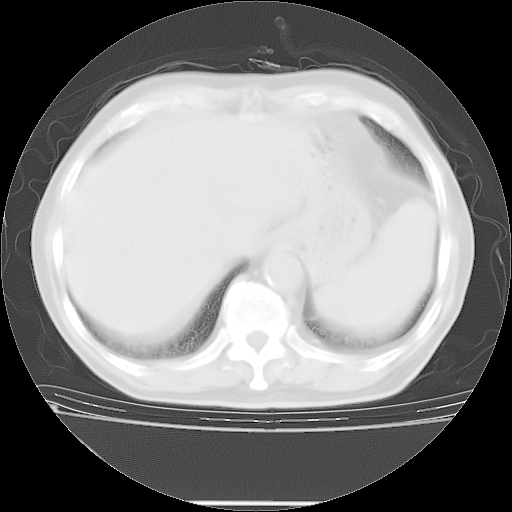

今天复查肺部CT,发现双肺广泛磨玻璃样改变。所以我把3月19日和5月9日相隔50天的肺部CT上传。请大家会诊。

5月9日肺部CT(在4月27日齐鲁医院肺部CT描述部分肺组织磨玻璃样改变,12天后肺组织广泛磨玻璃样改变)

大致读了系列胸部CT:纵隔窗无明显异常,肺窗:从4、27至今:主要是双肺中下野外带可见毛玻璃样改变,目前处于急性肺泡炎阶段,至于原因考虑1、结替组织或胶原血管性疾病所致?2、恶性疾病如恶组在肺部所致的表现或细支气管肺泡癌?3、药物或其它原因如肺蛋白沉着症所致肺泡炎目前不太可能?总之,明天就去请我院的呼吸科、感染科、血液科和临免专家会诊哈。